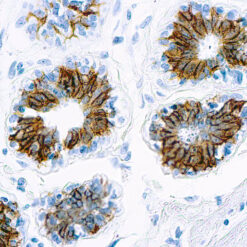

Prostate Specific Antigen, PSA

This product is intended for qualitative immunohistochemistry with normal and neoplastic formalin-fixed, paraffin-embedded tissue sections, to be viewed by light microscopy. Clinical interpretation of staining results should be accompanied by histological studies with proper controls. Patients’ clinical histories and other relevant diagnostic tests should be utilized by a qualified person(s) when evaluating and interpreting results.

| Cellular Localization | Cytoplasmic |

| Positive Control Tissue | Prostate carcinoma |